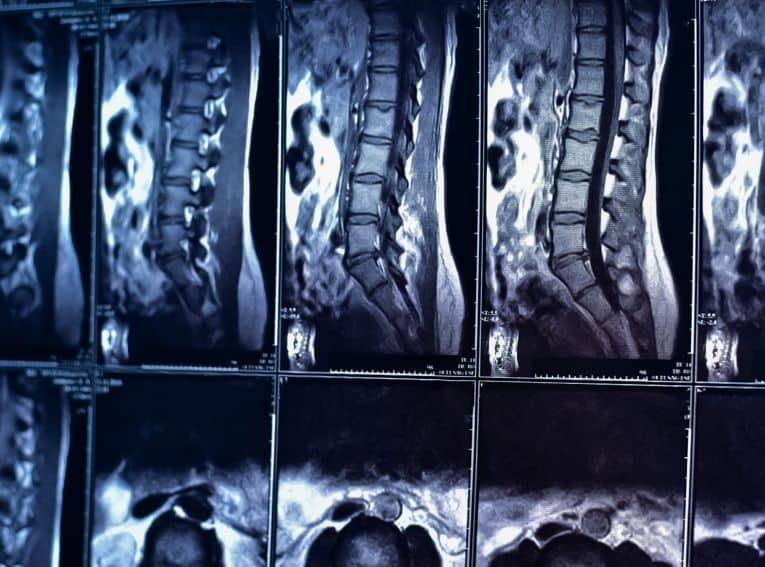

In addition to X-rays of the area to determine the precise location and severity of the bone fracture, a CT or MRI scan is also necessary to determine whether soft tissue has been damaged as well. Treatment is predicated on the extent of injury, if any, to the spinal cord, as well as on the nature of the cervical fracture.